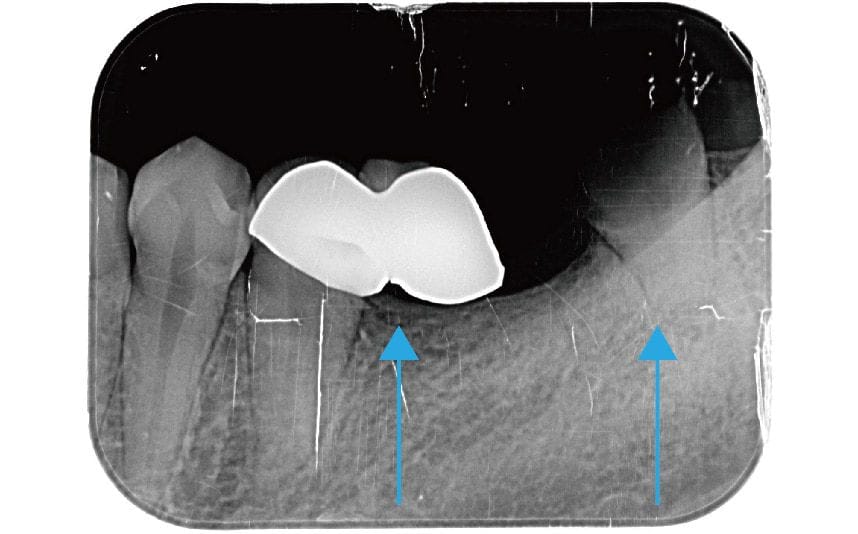

圖示:左下後牙區的假牙和臼齒殘根 圖示:左下後牙區X光片,箭頭處為假牙與臼齒殘根

圖示:假牙拆除前的X光片 圖示:假牙拆除前的X光片